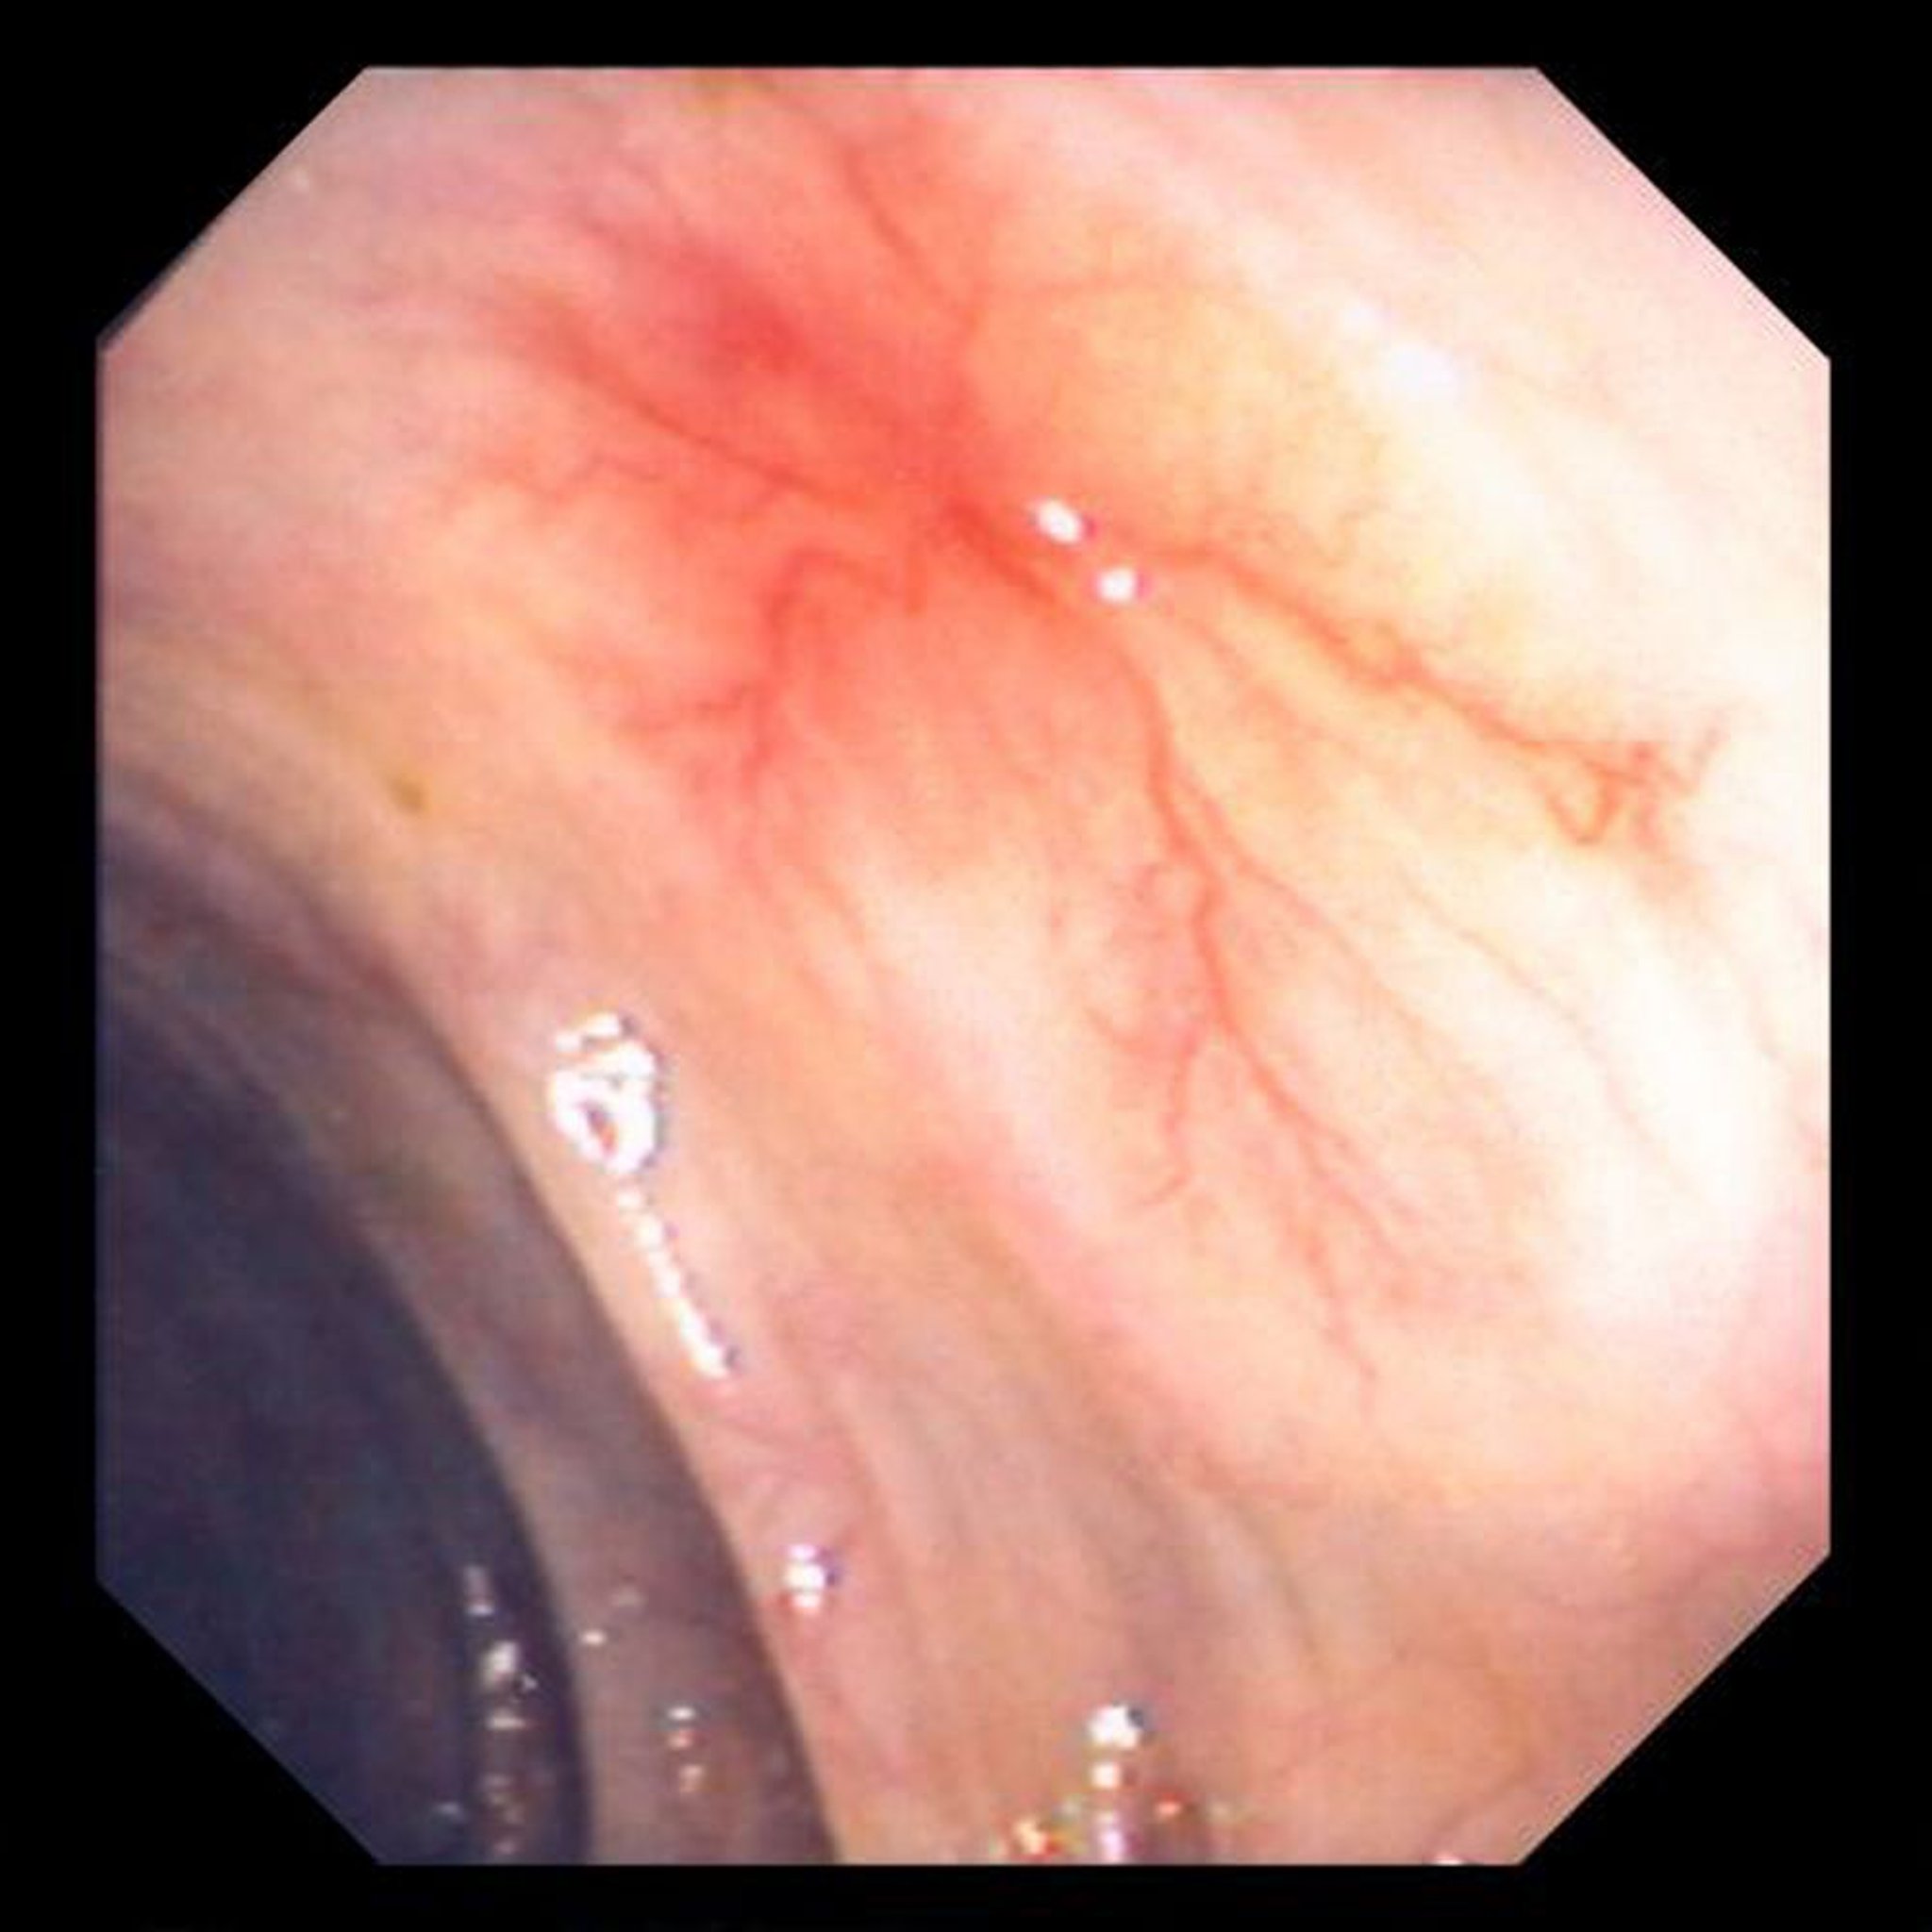

Ангиодисплазия

На данной фотографии показана сосудистая эктазия стенки кишечника.

Image provided by David M. Martin, MD.